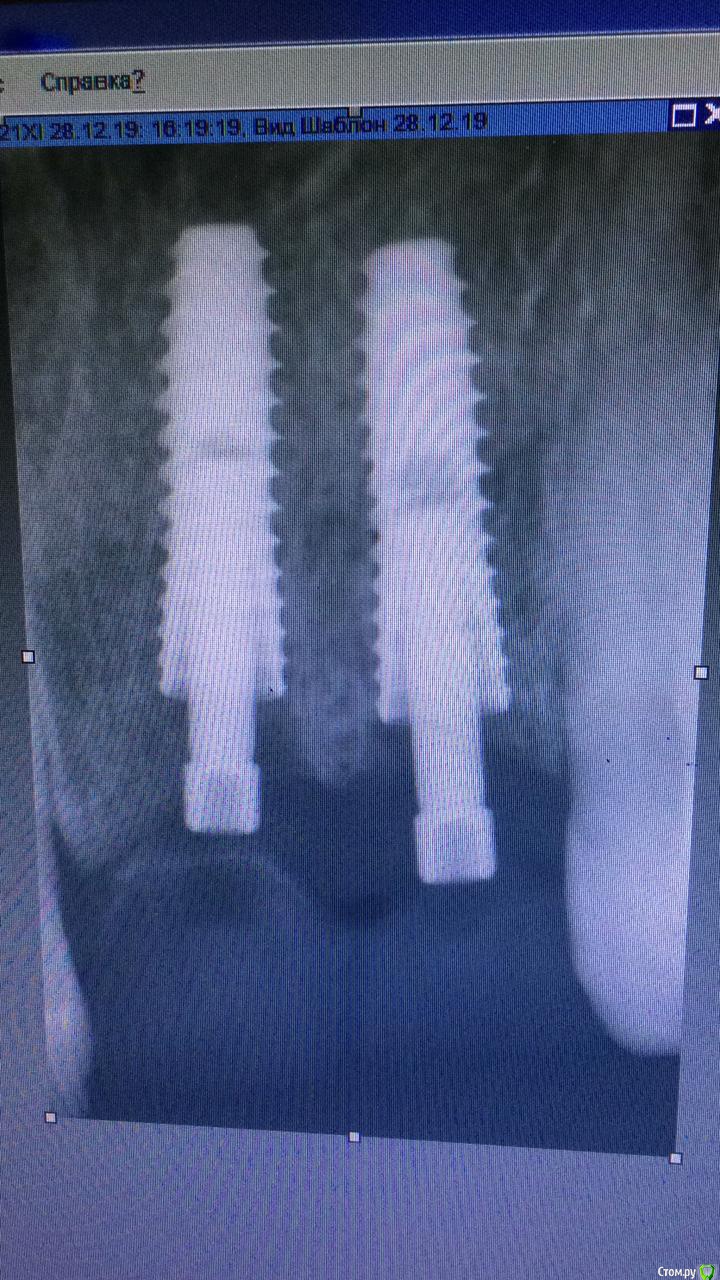

жулля Опубликовано 6 февраля, 2020 Автор Поделиться Опубликовано 6 февраля, 2020 Судя по всему, одна коронка недоприкручена, это может приводить к ее микроподвижности, попаданию пищи под десну. Ничего криминального, но, учитывая тот факт, что коронки связаны, я бы попробовал снять их и после проверки прикрутить заново. Но ситуация пограничная, сейчас период самый ненадёжный для механического воздействия на имплантаты, поэтому если в полости рта при осмотре доктор не видит повода для беспокойства, то, возможно, более рационально подождать ещё месяц-полтора, а пока в Вашу задачу будет входить идеальная гигиена вокруг имплантата с ежедневным использованием ирригатораСегодня была у ортопеда, он коронки просверлил, промыл хлоргексидином, потом подкрутил, замазал и отправил до субботы. Сказал, теперь все хорошо должно быть. В субботу пойду к имплантологу и там ортопед будет. Хочется надеяться на лучшее. Ссылка на комментарий

жулля Опубликовано 10 февраля, 2020 Автор Поделиться Опубликовано 10 февраля, 2020 Решила написать, после подкрутки непонятные ощущения прошли, но осталась небольшая болезненность при нажатии вдоль одного импланта. Хирург назначил лечение гомеопатическими препаратами, снимок не делал, смысла не увидел. Десна спала. Теперь пью лекарства. Болезненность при нажатии есть. Что это может быть. А так ничего не чувствую. Ссылка на комментарий

жулля Опубликовано 18 февраля, 2020 Автор Поделиться Опубликовано 18 февраля, 2020 Решила опять написать. 8 дней как пропила лекарства, частично боль ушла. Но боль при нажатии на десну вдоль импланта есть. . 3 месяца скоро будет 23.02. А так не болит ничего. ПРи надкусывании тоже боли нет. Это .наверное, отторжение уже. Ведь болей не должно быть как я понимаю совсем. Было ли такое в практике у кого? И понять шатается имплант или нет, не могу, так коронки качающиеся изначально Ссылка на комментарий

Irouil Опубликовано 19 февраля, 2020 Поделиться Опубликовано 19 февраля, 2020 Нужны фото во рту и больше срезов, особенно в области шейки имплантатов, если есть у Вас весь снимок попробуйте выложить его. Судя по тому, что предоставленно, болевые ощущения связаны с давлением края имплантата на десну. Если имплантат выступает не сильно, то это поправимо пересадкой десневого трансплантата над этим местом. И ещё не совсем ясно:И понять шатается имплант или нет, не могу, так коронки качающиеся изначальноКоронки Вам же зафиксировали, они до сих пор подвижны? Ссылка на комментарий